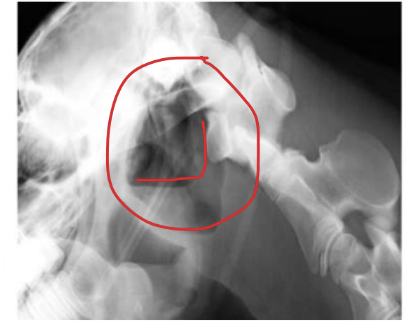

Q

This is a latero-lateral view of the head. What abnormal findings are present?

A

Guttural pouch with chondroids

* Pus within the guttural pouches was not evacuated; remained, dessicated and formed chondroids

* These contain visible bacteria within them

* Bacteria can survive in here for a very long time

* Must remove chondroids to clear the infection and then treat